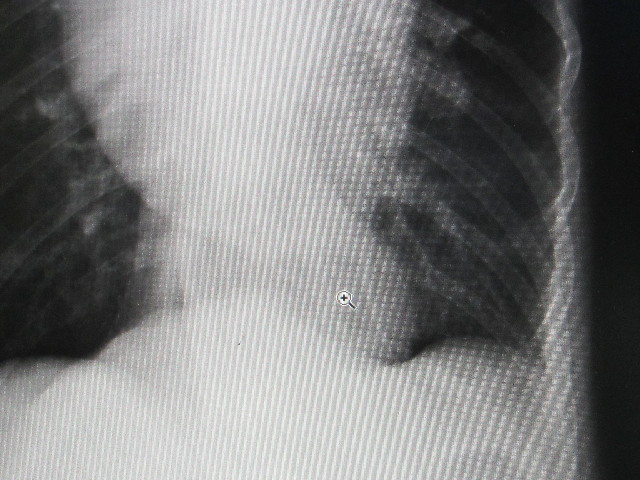

今日、獣医さんでレントゲンを撮って、Qちゃん(食道の大きさを調べてもらいました。

●食道の腫瘍のレントゲン

手前(お口側46.062mm(10月10日は46.939mmなので0.877mm小さくなった)

奥(胃の入り口)61.008mm(10月10日は59.192mmなので1.816mm大きくなった)

巨大食道症の所見はないそうです。

先生的には大きくなったかどうかよくわからないとのことです。

+のポンターのある、大きな風船状のものがべべちゃんの食道の腫瘍です。